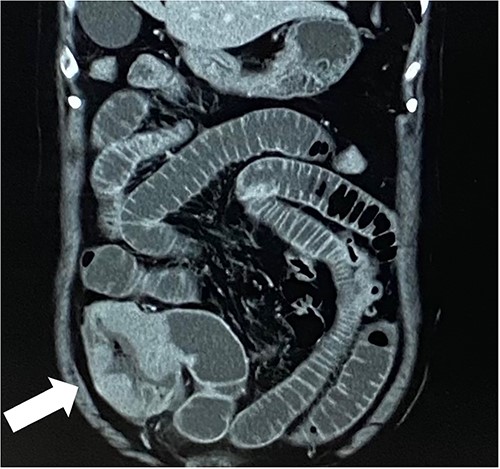

A 79-year-old woman, who had been taking MTX 4.0 mg/week for rheumatoid arthritis since she was 64 years old, came to our hospital complaining of vomiting repeatedly. Physical examination revealed no tenderness in the abdomen, but the abdomen was distended and a mass was observed in the right lower abdomen. Contrast-enhanced computed tomography revealed a mass lesion with contrast effect in the cecum and multiple peritoneal tumors (Figs 1 and 2).

In this case, the patient was found as a colorectal mass and was suspected to have peritoneal dissemination.

It was accompanied by small bowel obstruction, and bypass surgery was performed. The histopathological diagnosis of the disseminated nodule was also a result of DLBCL.